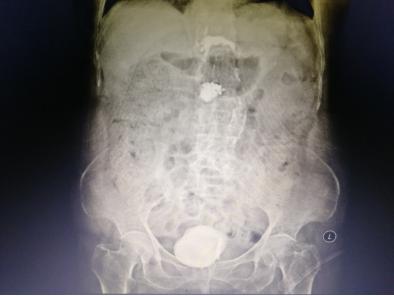

入院后,经过专业的全面系统检查后,我院泌尿外科专家组针对李老太病情召开了联合会诊。李老太的结石犹如鹅蛋般大小,而且已引起一系列严重并发症,不及时取出结石将造成更严重后果,对于一个91岁高龄而且身体情况欠佳的老太太来说采取哪种手术方案都有弊有利。

暨南大附属一院泌尿外科卓育敏主任分析:“为她选择治疗方案的时候必须慎重,因患者年龄大,多项器官功能都有明显衰退而且膀胱已无多少操作空间,开放手术虽很快可以完成,但一个7-8公分的伤口对她来说就是一个很大的创伤,很容易发生脂肪液化,尿漏等并发症,这对老人都可能造成不可预测的影响。而采用经尿道手术近乎无创,但这种结石最坚硬,又那么大,手术时间肯定很长,医生累且不说,一台高功率碎石机连续多小时的工作可能都扛不住会死机,要准备2台机器轮番上阵,要避免器械对老太膀胱黏膜损伤。”

此外,患者腰椎处压缩骨折,骨质疏松严重,心肺功能差,对麻醉的选择也是一种考验。专家团队仔细分析后,决定给老太太行细针硬外麻经尿道肾镜钬激光膀胱碎石取石术。一根纤细的纤维肾镜轻松地进入了老太太的膀胱,可以见到膀胱内的巨大结石与膀胱壁几乎紧密接触,找到缝隙后一点一点逐步击碎结石,将结石粉末化处理,并用吸引器将膀胱内碎石多次吸出,反复多次,最终将结石干净彻底清楚。手术圆满成功,手术进行了近4个小时,患者术中情况生命体征都很稳定。